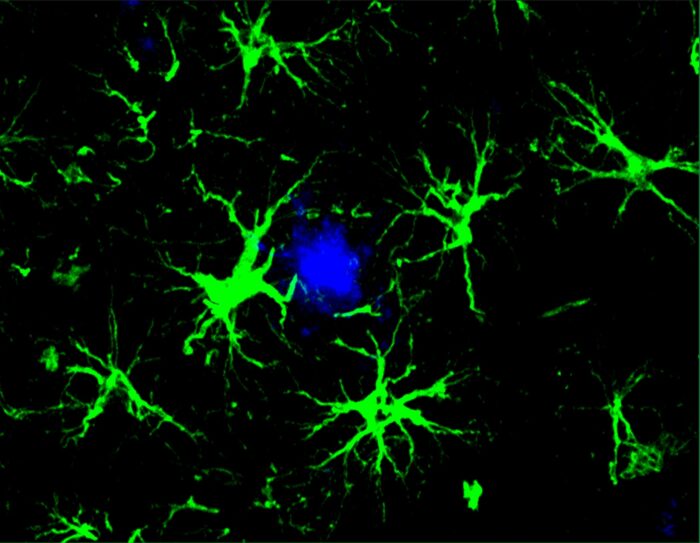

astrocytes in green surrounding harmful brain plaques in blueYun Chen

Like CAR-T cell therapies used for cancer treatment, in which T cells of the immune system are genetically modified to attack cancer cells, this new approach equips cells — in this case, brain cells called astrocytes — with a CAR homing device to grab onto a target for destruction. These new CAR-astrocyte cells have features that transform them into super cleaners that remove damaging proteins from the brain that play a role in cognitive decline.

To reduce the cleaning burden on microglia, first author Yun Chen, PhD, then a graduate student in the labs of Colonna and David M. Holtzman, MD, the Barbara Burton and Reuben M. Morriss III Distinguished Professor of Neurology at WashU Medicine, transformed astrocytes, the most abundant cell type in the brain, into amyloid-cleaning machines. He custom-designed and delivered a gene to astrocytes that codes for the chimeric antigen receptor (CAR) via a harmless virus injected into mice. The CAR, now present on the surface of astrocytes, enabled the cells to capture and engulf amyloid beta proteins. With their newly acquired ability, the astrocytes — generally responsible for keeping the brain tidy — concentrated their efforts on only cleaning amyloid beta plaques in mice prone to its buildup.